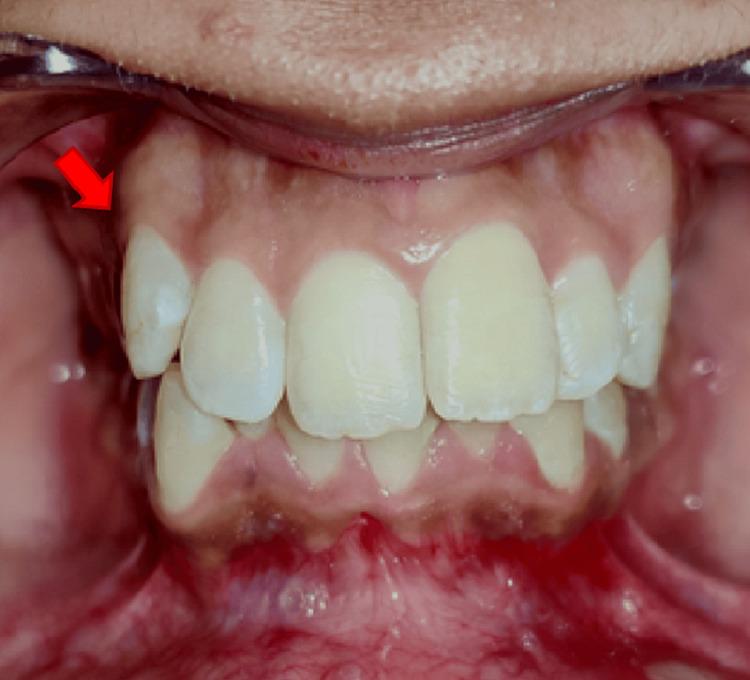

牙髓感染主要涉及革兰氏阴性厌氧菌菌群,由于这种感染,根尖周区域会发生免疫反应,这被称为根尖周病变。这种病变在X射线上可能表现为透射(暗)区,表明根尖周炎症和感染。其患病率取决于年龄、口腔卫生维护和牙科护理等因素。男性比女性更容易受到这种感染的影响。根尖周病变有两种治疗方式:手术或非手术牙髓治疗。改良三联抗生素糊剂(TAP)由环丙沙星、甲硝唑和克林霉素按1:1:1的比例配制而成,最初是专门为治疗牙髓坏死的牙齿而制备的,并支持牙齿复活和再生方案。该治疗在消除根管系统中的细菌方面非常成功。它对多种通常与牙髓感染相关的细菌具有广谱抗菌活性。改良TAP通常在根管内放置预定时间,然后取出,接着进行根管冲洗,这有助于从根管中清除微生物。非手术治疗应始终优先于手术方法,以避免更具侵入性的操作。

Infection of the dental pulp involves mainly Gram-negative, anaerobic bacterial flora and due to this infection, the periapical area experiences an immunological response, which is termed a periapical lesion. This lesion may appear as a radiolucent (dark) area on X-rays, which indicates periapical inflammation and infection. Its prevalence depends on factors such as age, oral health maintenance, and dental care. Men are more likely to be affected by this infection than women. There are two modalities for the treatment of periapical lesions: surgical or non-surgical endodontic therapy. The modified triple antibiotic paste (TAP) comprising ciprofloxacin, metronidazole, and clindamycin in the ratio of 1:1:1 was first prepared expressly to treat the teeth with necrotic pulp and to support the protocol for revitalization and regrowth. The treatment was very successful in eliminating germs from the root canal system. It provides broad-spectrum antimicrobial activity against a wide range of bacteria commonly associated with endodontic infections. The modified TAP is usually inserted into the canal for a predetermined amount of time and then removed followed by the irrigation of root canal, which helps to eliminate the microorganisms from the root canal. The non-surgical treatment should always be the first choice over the surgical approach so as to avoid a more invasive procedure.